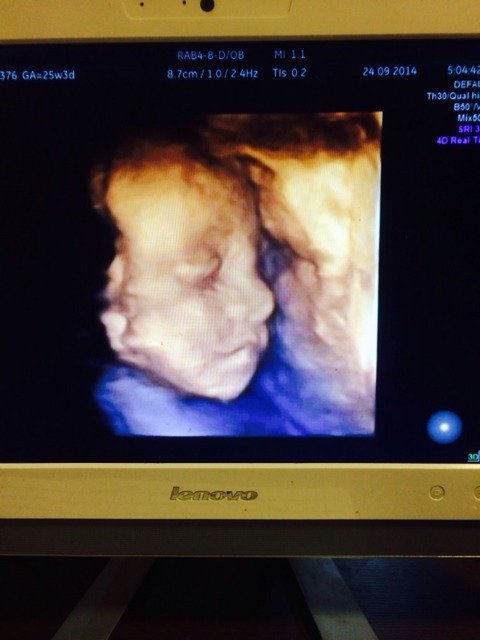

我宝宝的四维照片,22周时候拍的 点击展开 小安/ 2014-11-02 04:26 为您推荐: 其他回答 你好啊。是接近正面的照片呢,按时产检啊,祝你生个健康的 宝宝 文斯6 2014-11-02 20:18 相关问题 我宝宝的四维照片,22周时候拍的,可爱不? 孕37周,没做过四维,做彩超都说宝宝很好,有没有事 24周零4天去做四维彩超,宝宝体重大约是1 82斤,是大还是小啊?